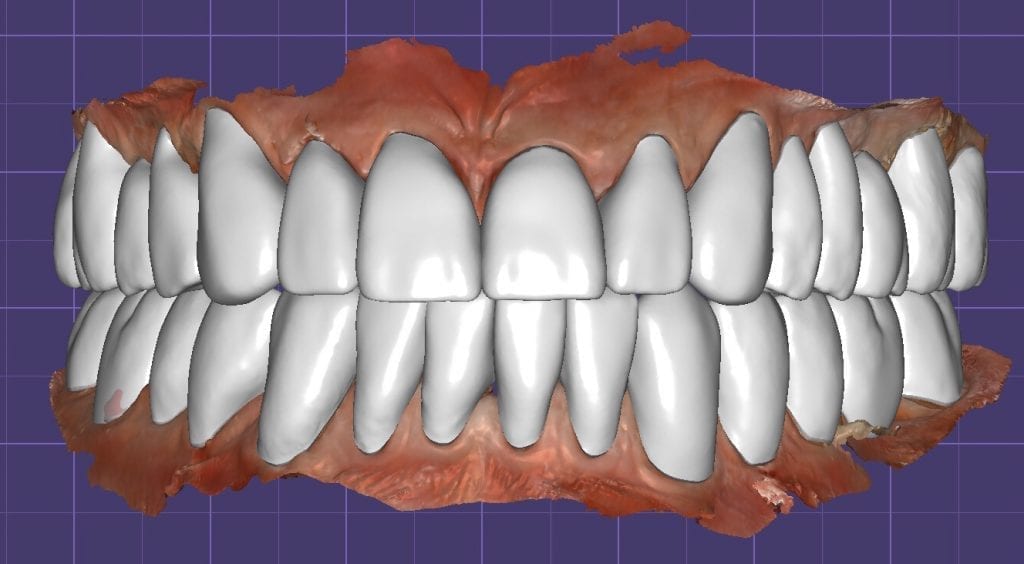

The digital models were then imported into a third party software where a library of tooth morphologies are available for the clinician to choose from.

Once the appropriate library is chosen, the digital wax ups are performed. In the subsequent photos you can see the transparent overlay of the wax-ups to the original position of the existing dentition